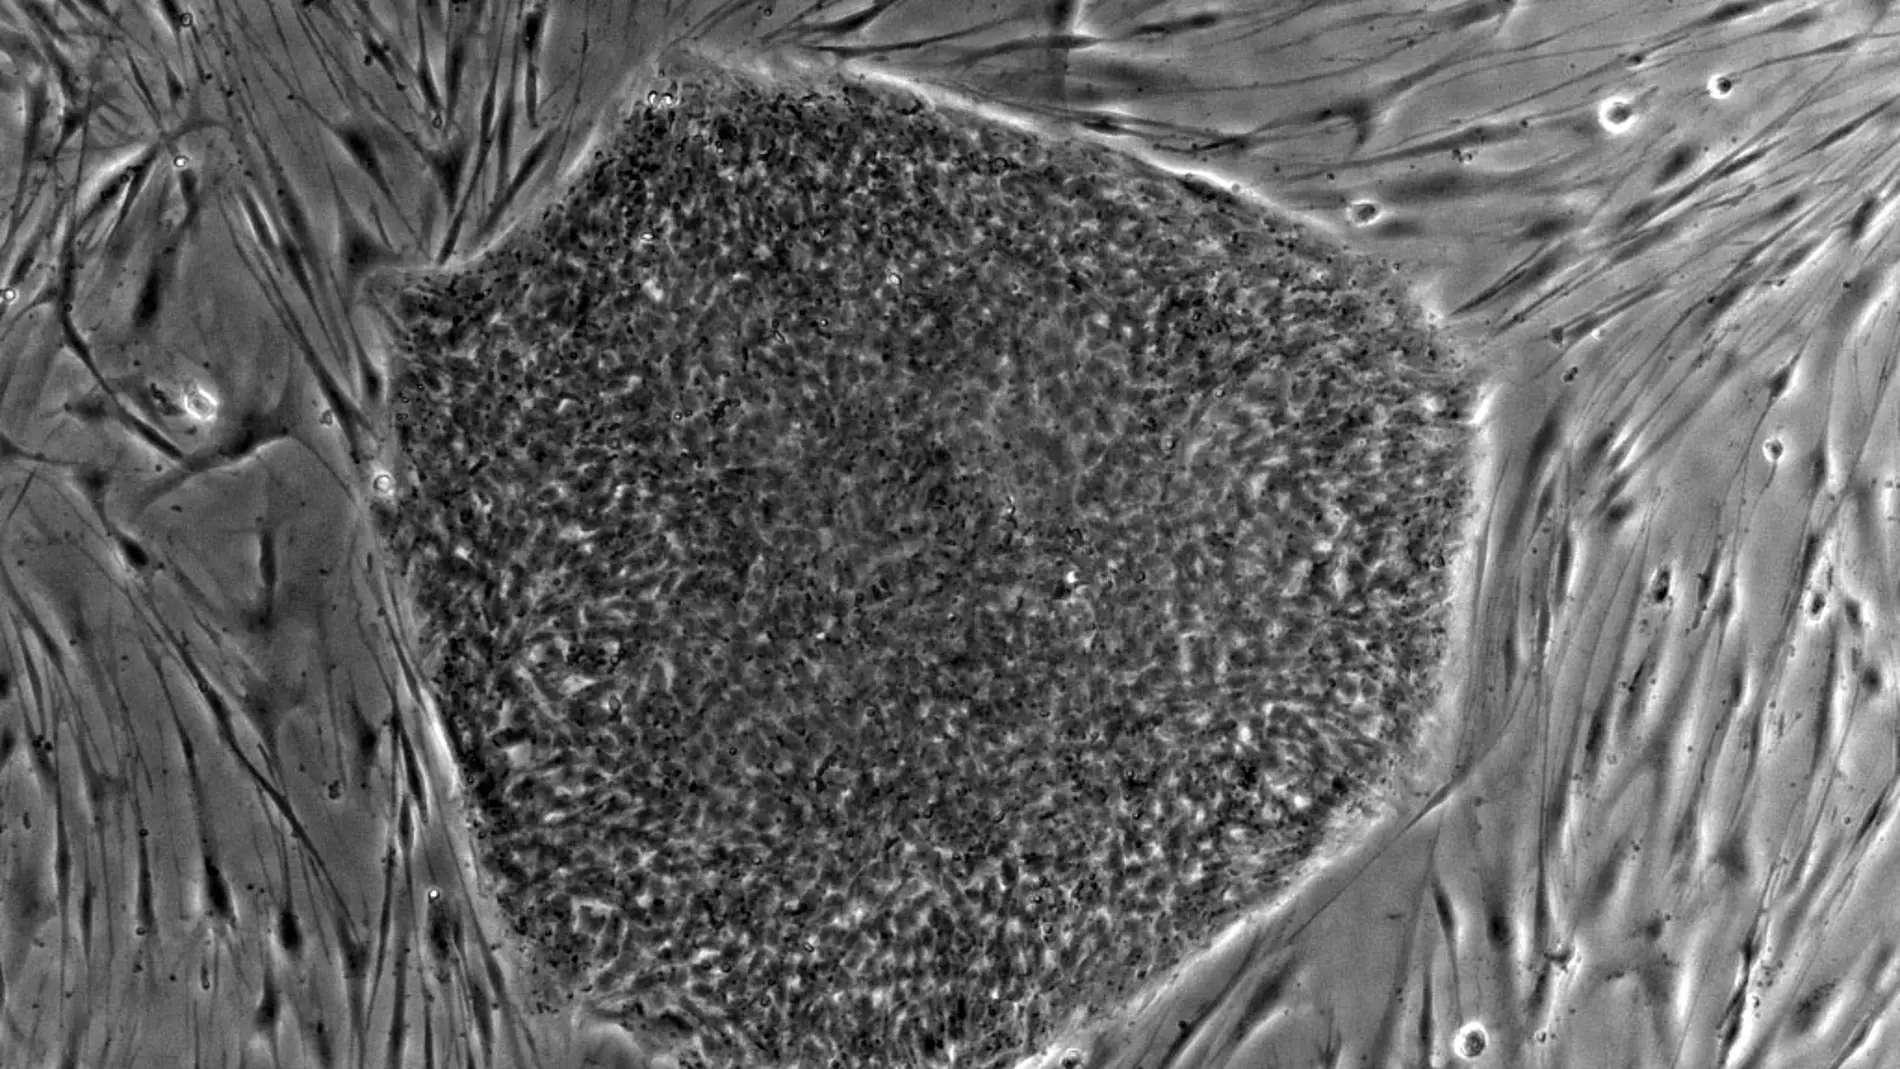

Ahora, investigadores de todo el mundo reunidos en el proyecto Grandiose han explorado paso a paso los caminos de la reprogramación y han descubierto un nuevo tipo celular resultante del proceso: las células de clase F, llamadas así por el adjetivo fuzzy (borroso, en inglés), por la apariencia de las colonias que forman. Estas células son estables, lo que podría facilitar su uso terapéutico. Además, los nuevos detalles observados en el estudio permitirán controlar mejor el proceso. Los resultados se publican en una serie de cinco artículos en las revistas Nature y Nature Communications.

Dos de los artículos revelan detalles del proceso de reprogramación que determinan los tipos de células que se obtienen de ella. Gracias a ese examen exhaustivo, los investigadores han identificado las células de clase F como un tipo diferente a las ya conocidas.

Las F proliferan a gran velocidad y son estables, lo que, en principio, podría ser útil para producir células a gran escala, un requisito necesario en las futuras terapias regenerativas para combatir enfermedades, como la diabetes. Su capacidad de reproducción “es positiva, pero la aplicación clínica todavía no es segura, porque las mutaciones derivadas de la inserción podrían formar tumores”, explica Izpisua Belmonte.